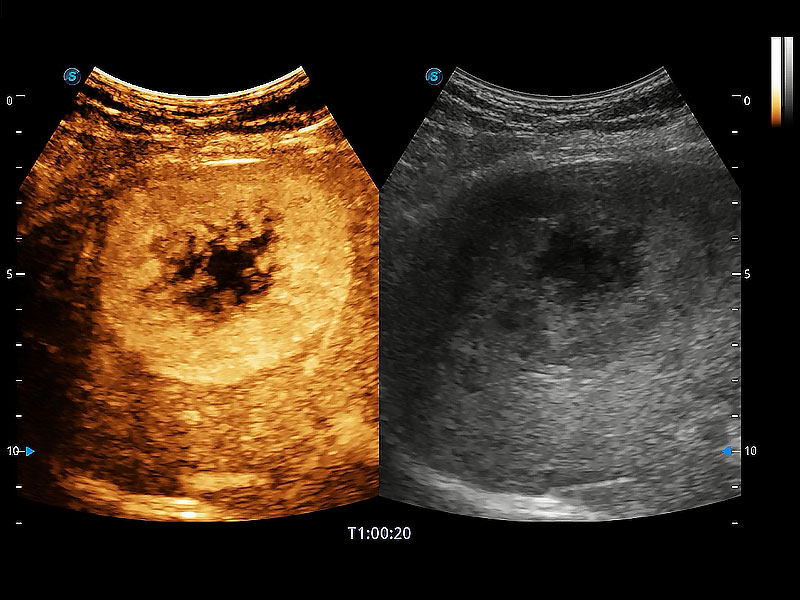

非線性融合造影成像充分利用諧波和基波信號(hào),為難以觀察的血流進(jìn)行增強(qiáng)顯像??捎糜诰€陣、凸陣、微凸陣、相控陣探頭。